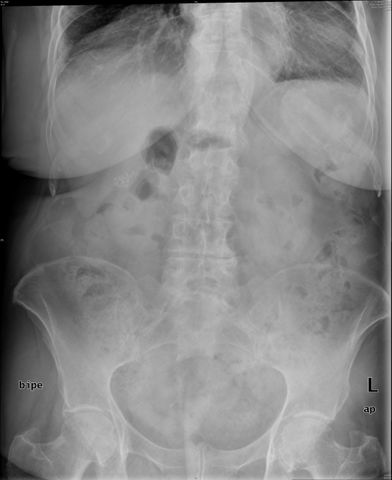

Diverticulosis de colon.

Diverticulosis de colon. Megacolon.